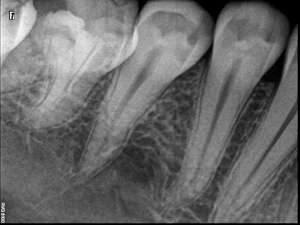

Avant

Après